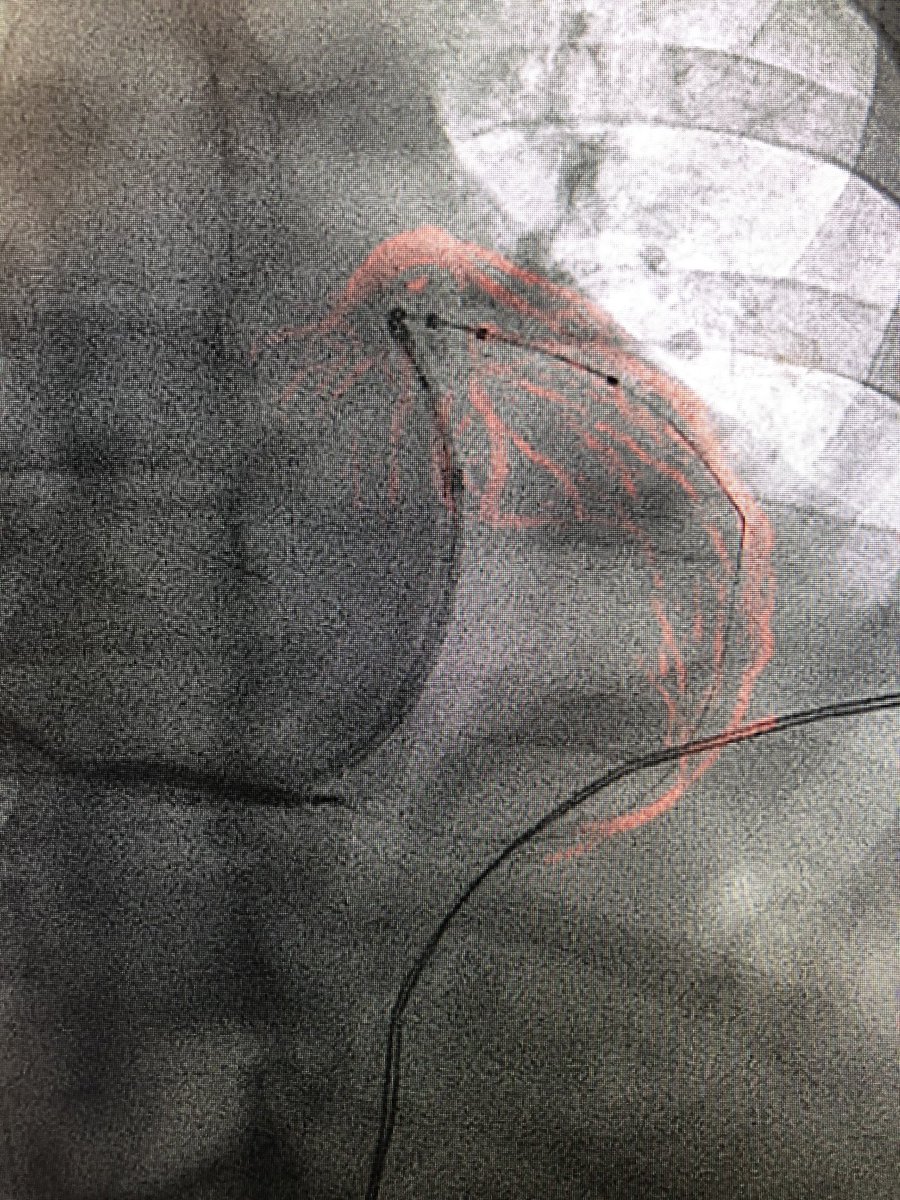

Coronary Sinus Injection for Bi-V ICD placement Using

#Philips#Dynamic#Coronary#Roadmap#EPLab#PhilipsIGT@PhilipsHealth@PhilipsNApic.twitter.com/sQ8W5ib9QD